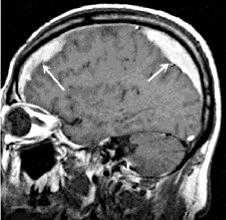

На контрольной КТ головного мозга в послеоперационном периоде видна положительная динамика: состояние после краниотомии, репозиции вдавленных фрагментов теменной кости, удаления субдуральной гематомы, регресса дислокации срединных структур стабильное.

Эта тактика в косметическом и лечебном плане выгоднее, чем чаще применяемая резекционная трепанация при вдавленном переломе, когда деформированный фрагмент кости выкусывается, формируется дефект кости, который закрывается краниопластиной либо сразу же, либо уже при повторном оперативном вмешательстве.